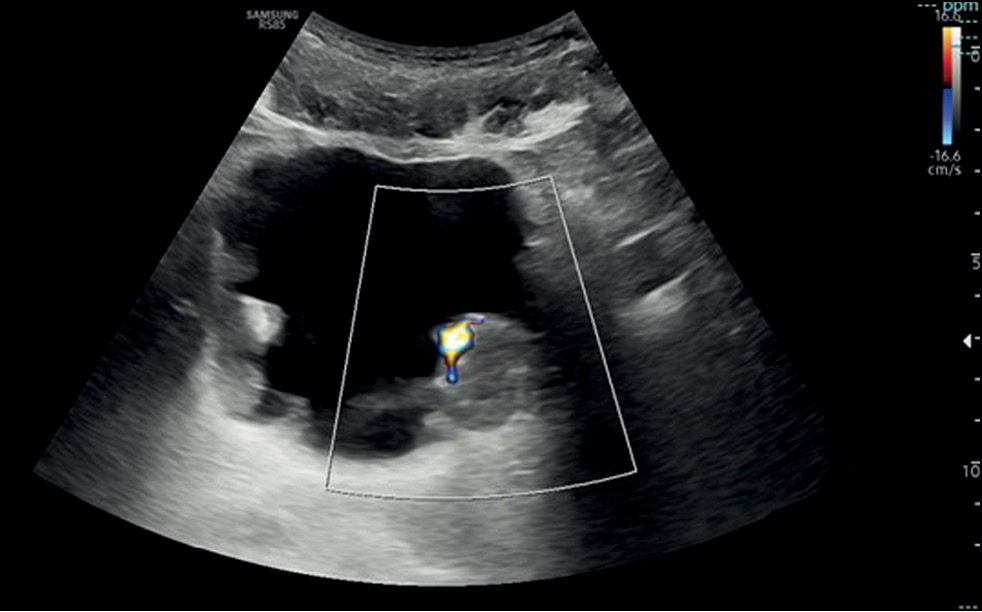

Comparison of the diagnostic accuracy of whole-body diffusion-weighted imaging and 18F-prostate-specific membrane antigen-1007 positron emission tomography combined with computed tomography for detecting bone metastases in prostate cancer

Abstract

BACKGROUND: The increasing availability of 18F-prostate-specific membrane antigen-1007 (18F-PSMA-1007) for prostate cancer staging highlighted its advantages, particularly its higher spatial resolution compared to analogs. Moreover, accumulating scientific data indicate an increase in false-positive findings, predominantly in bones, which may lead to unwarranted upstaging of the disease. Diffusion-weighted imaging may be used for the early detection of bone metastases.

AIM: This study aimed to assess and compare the diagnostic accuracy of whole-body 18F-PSMA-1007 positron emission tomography combined with computed tomography and whole-body and pelvic bone diffusion-weighted imaging in patients with prostate cancer.

METHODS: A retrospective single-center selective study was conducted. The imaging results of 119 patients with prostate cancer were divided into two groups: group 1 comprised 40 pairs of 18F-PSMA-1007 positron emission tomography combined with computed tomography and whole-body diffusion-weighted magnetic resonance imaging scans, and group 2 included 79 pairs of similar studies, with magnetic resonance imaging performed only for the pelvic bones. The diagnostic studies were performed at an inter-study interval ≤14 days. The metastatic bone lesions detected in different anatomical regions was counted using data from 18F-PSMA-1007 positron emission tomography combined with computed tomography and magnetic resonance imaging. Lesions were considered true positives if confirmed by additional magnetic resonance imaging pulse sequences and/or follow-up observation.

RESULTS: Whole-body diffusion-weighted imaging demonstrated higher specificity (58.1%) for detecting bone metastases than 18F-PSMA-1007 positron emission tomography combined with computed tomography (51.06%). However, its sensitivity was lower: 93.22% versus 97.55%.

CONCLUSION: Despite its advantages, 18F-PSMA-1007 positron emission tomography combined with computed tomography shows a high rate of false-positive bone findings. These are most commonly noted in the ribs, vertebrae, and pelvic bones. Suspicious bone lesions should be further evaluated to avoid unjustified disease upstaging. Thus, whole-body magnetic resonance imaging with diffusion-weighted sequences and selective fat signal suppression can be used.